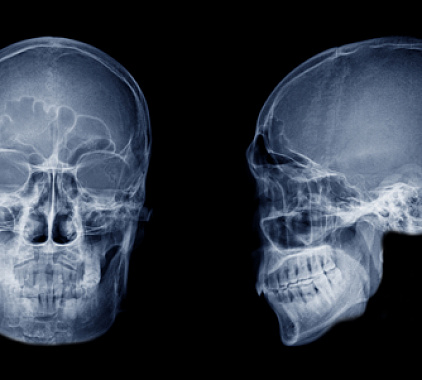

Как делается рентген пазух носа

Пациент приходит к назначенному времени, врач разъясняет, что показывает рентген носовых пазух и как проходит процедура. В кабинете рентген-лаборант помогает занять нужную позу, закрывает щитовидную железу и грудь защитным фартуком, кратко объясняет, куда смотреть и как дышать. Рентгеновский аппарат выполняет экспозицию, и изображение сразу видно на экране. Выбор проекций зависит от клинической задачи и предполагаемого заболевания — именно они определяют, что будет лучше видно.

- Обзорная прямая. Универсальный старт: видно носовую полость, симметрию синусов, велик ли объем «затемнения». Такой формат рентгена пазух носа подходит для экспресс-оценки и контроля после лечения.

- Боковая. Помогает оценить верхнезадние отделы, хоаны, соотношение структур носоглотки. Подразумевает рентген носовых пазух в боковой проекции, когда врачу важен «профиль» анатомии.